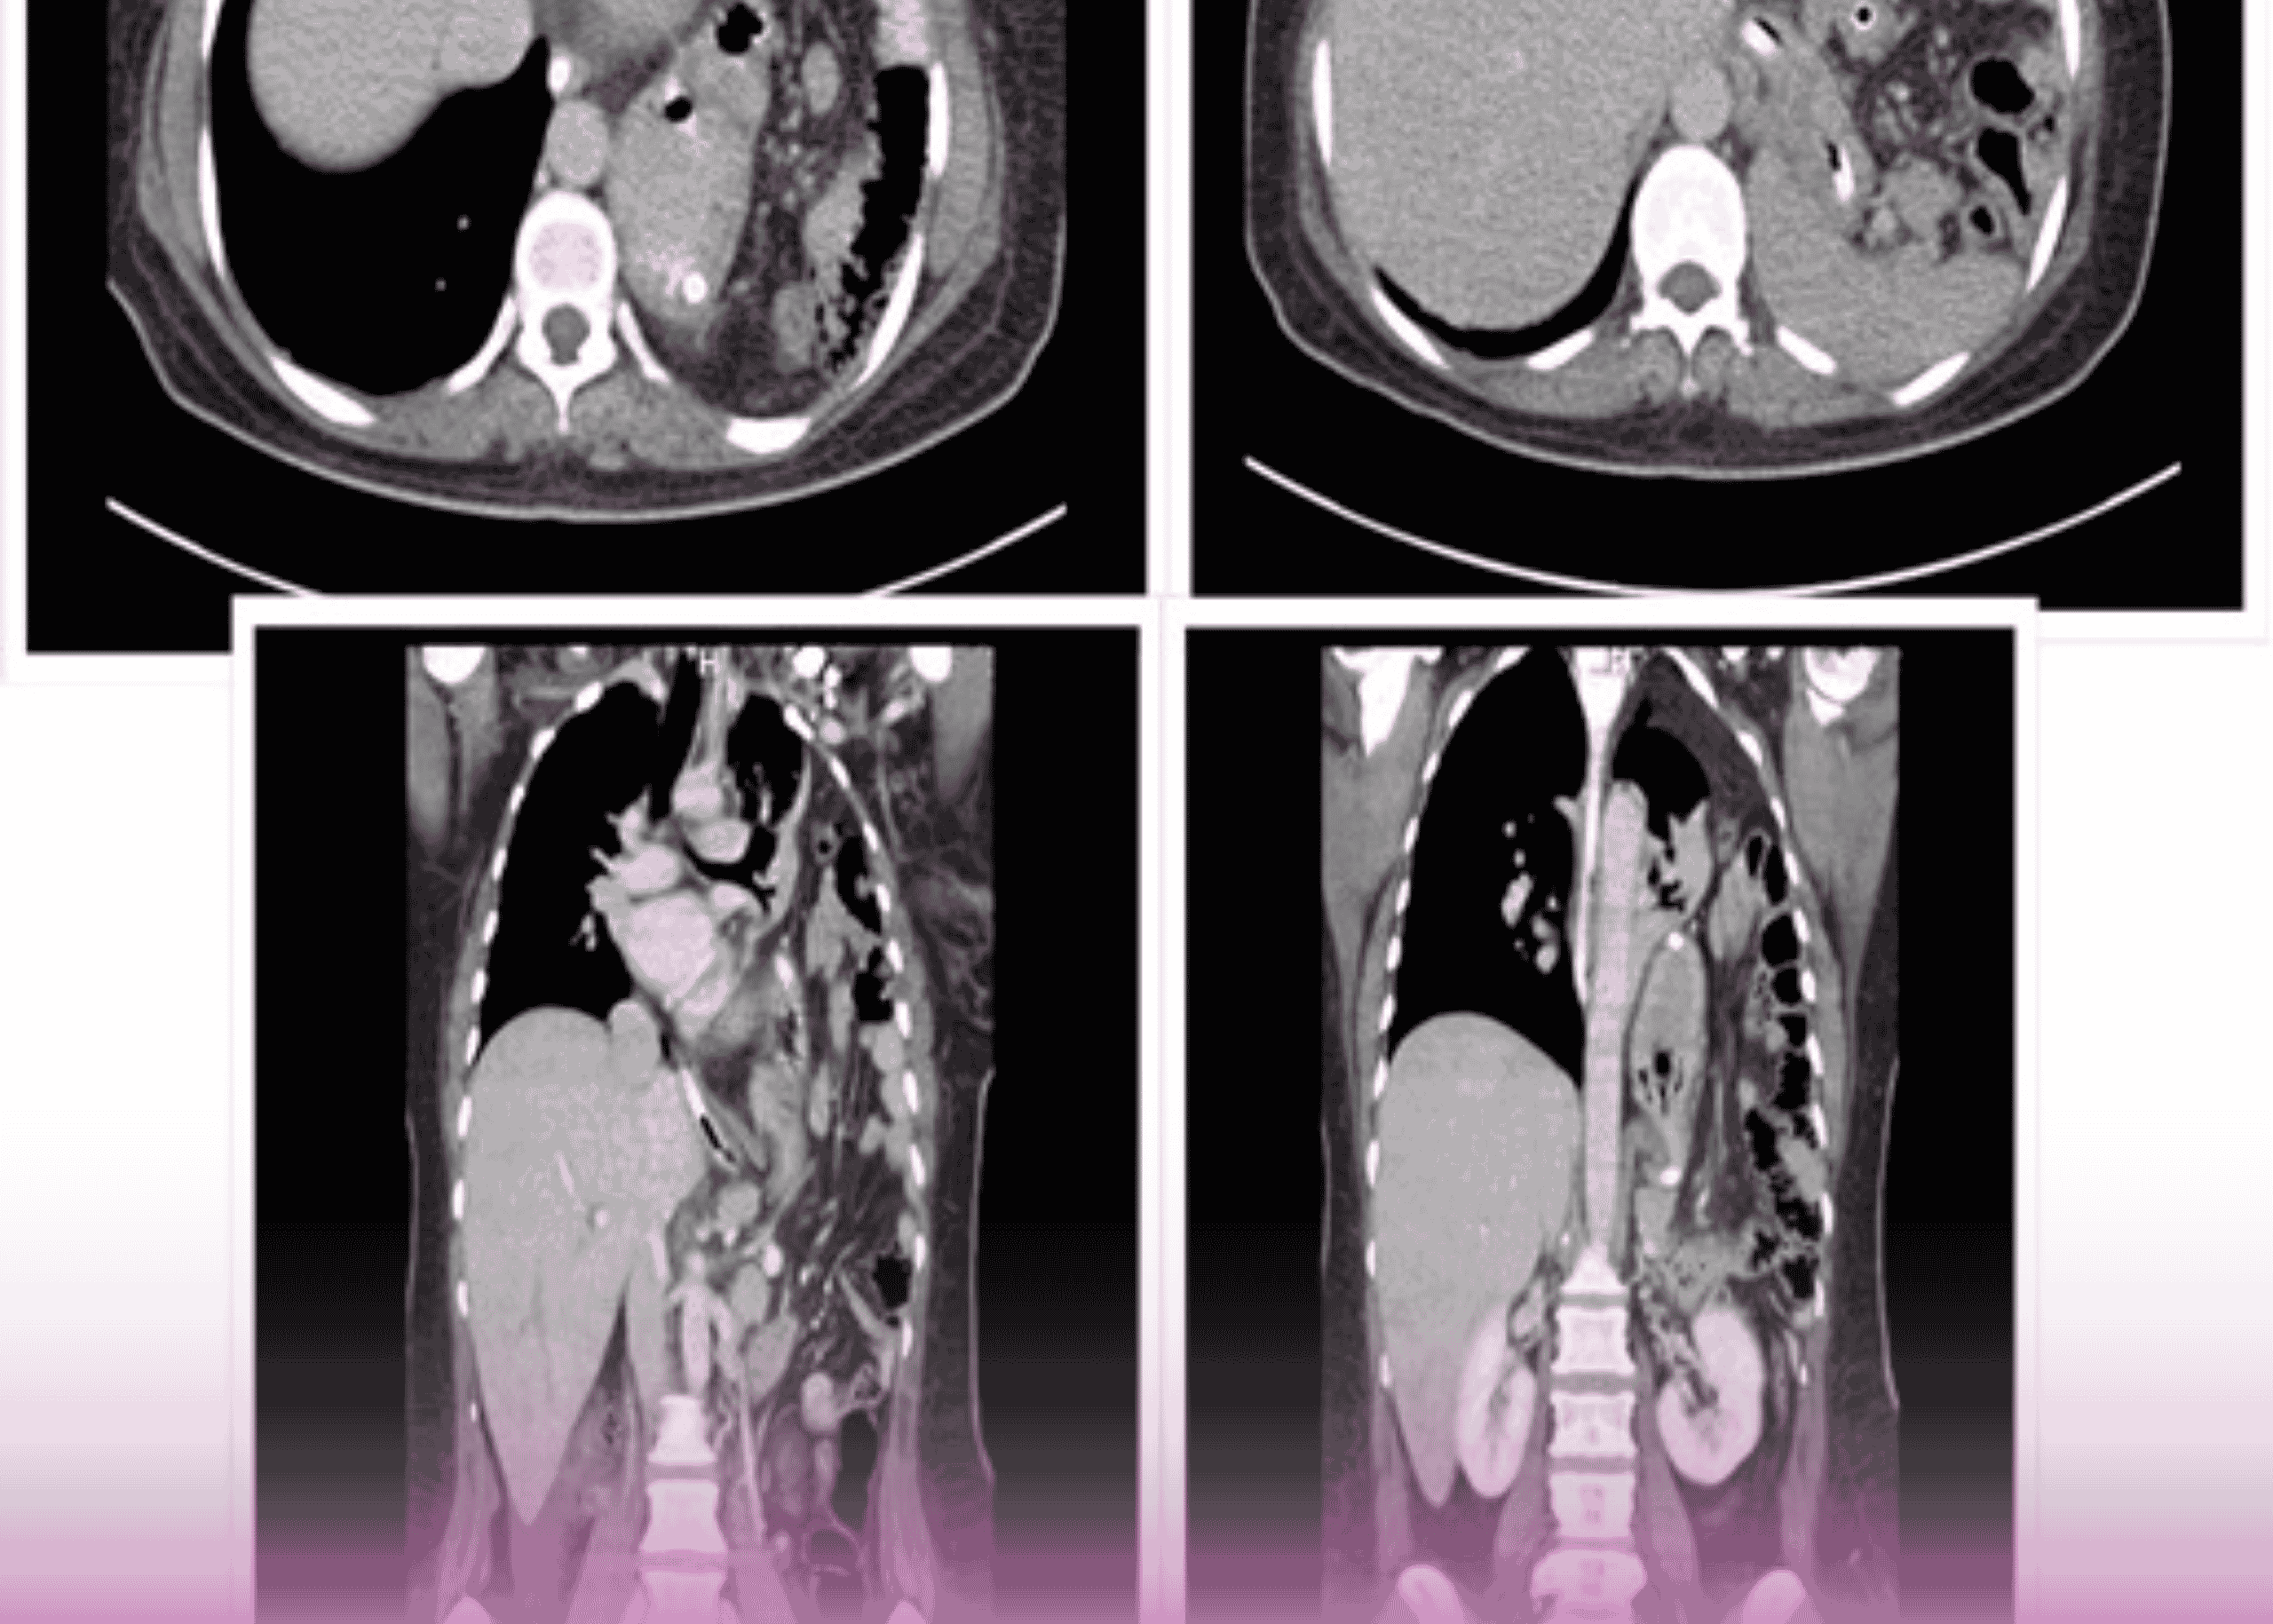

فتق الحجاب الحاجز ما بعد الرضح: التدبير الجراحي لحالة معقدة باستخدام المدخل الصدري البطني

مقدمة تمثل الفتوق الحجابية تحدياً جراحياً كبيراً، خاصة عندما تكون كبيرة وتحتوي